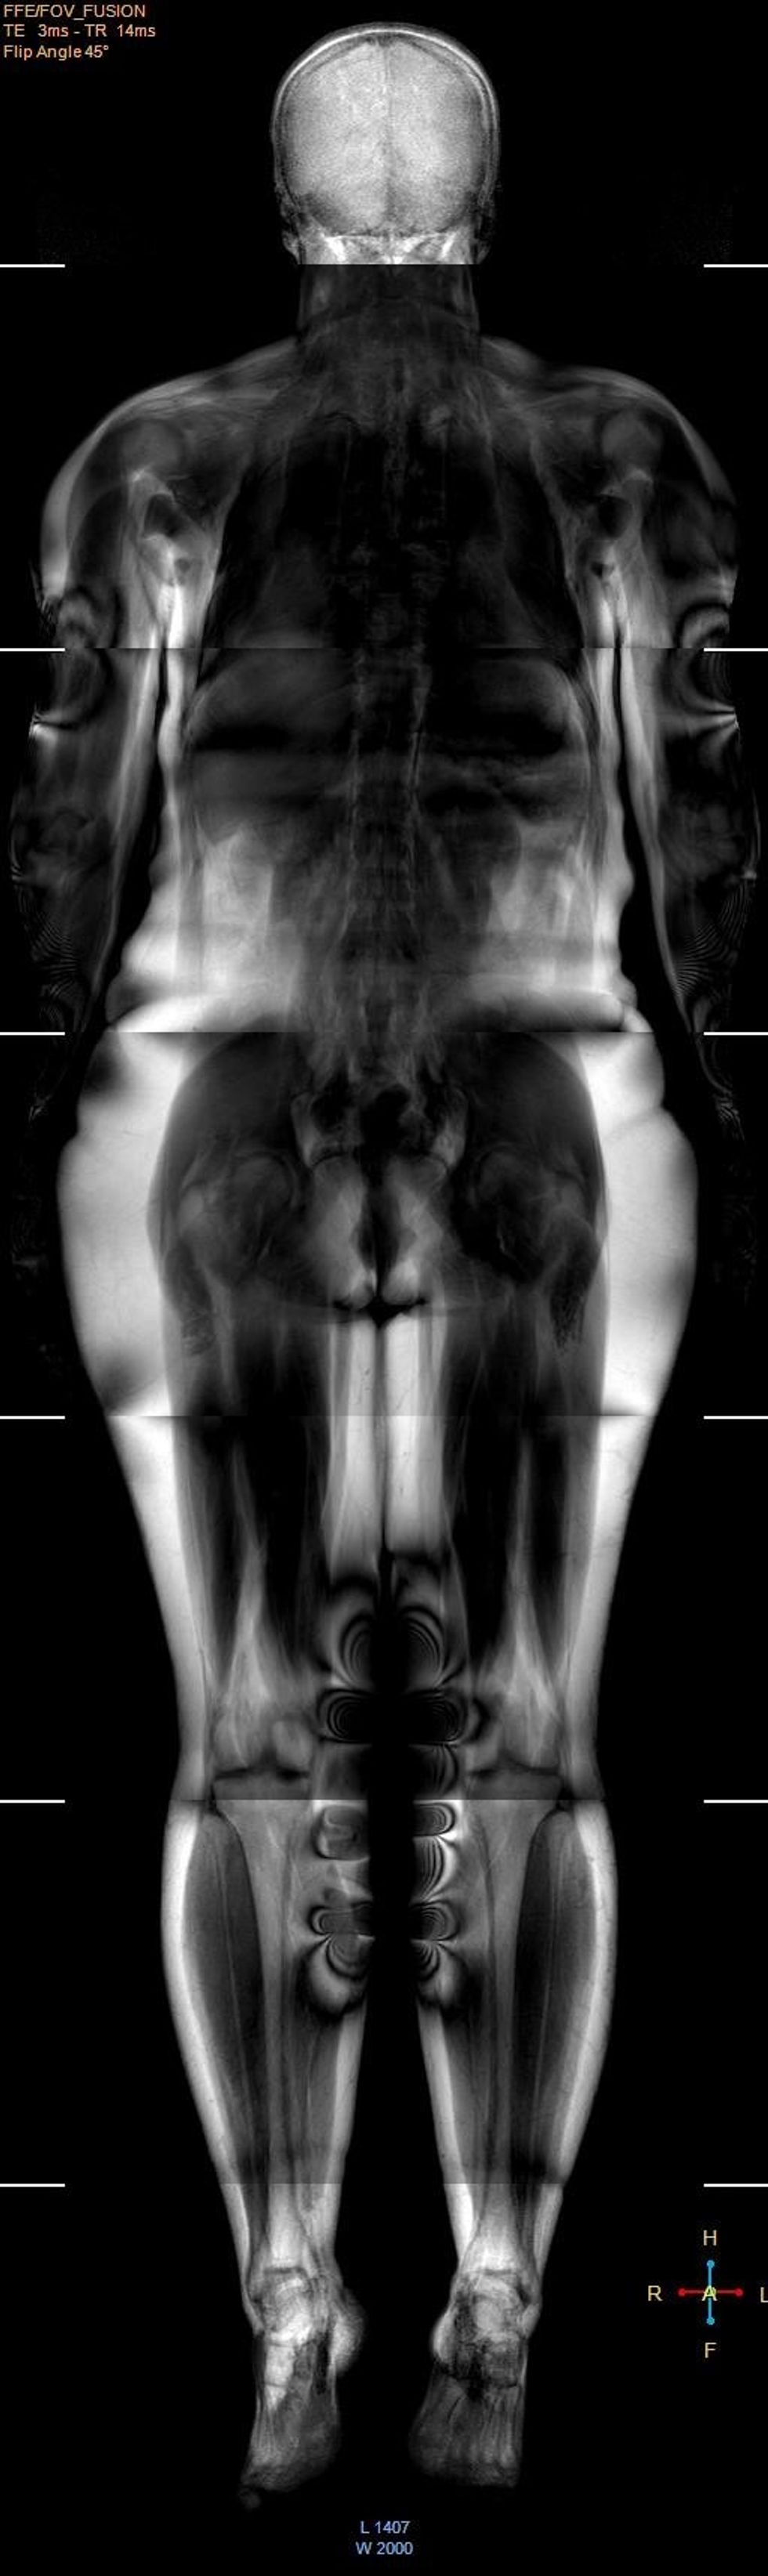

Në Klinikën e Radiologjisë të QKUK-së për herë të parë kryhet Rezonanca Magnetike e tërë trupit

Shërbimi Spitalor Klinik dhe Universitar i Kosovës ka njoftuar se në Klinikën e Radiologjisë të QKUK-së, është realizuar për herë të parë Rezonanca Magnetike e tërë trupit.

"Kompletimi i programeve softuerike, trajnimi i personelit dhe organizimi i shërbimeve tjera, mundësuan që të bëhet ky incizim i avancuar. Nevojat e popullatës dhe të klinicistëve për këtë incizim shumë të shtrenjtë, janë ekstremisht të mëdha dhe në të ardhmen planifikohet organizimi adekuat i këtij shërbimi për pacientët", thuhet në njoftim. /Telegrafi/